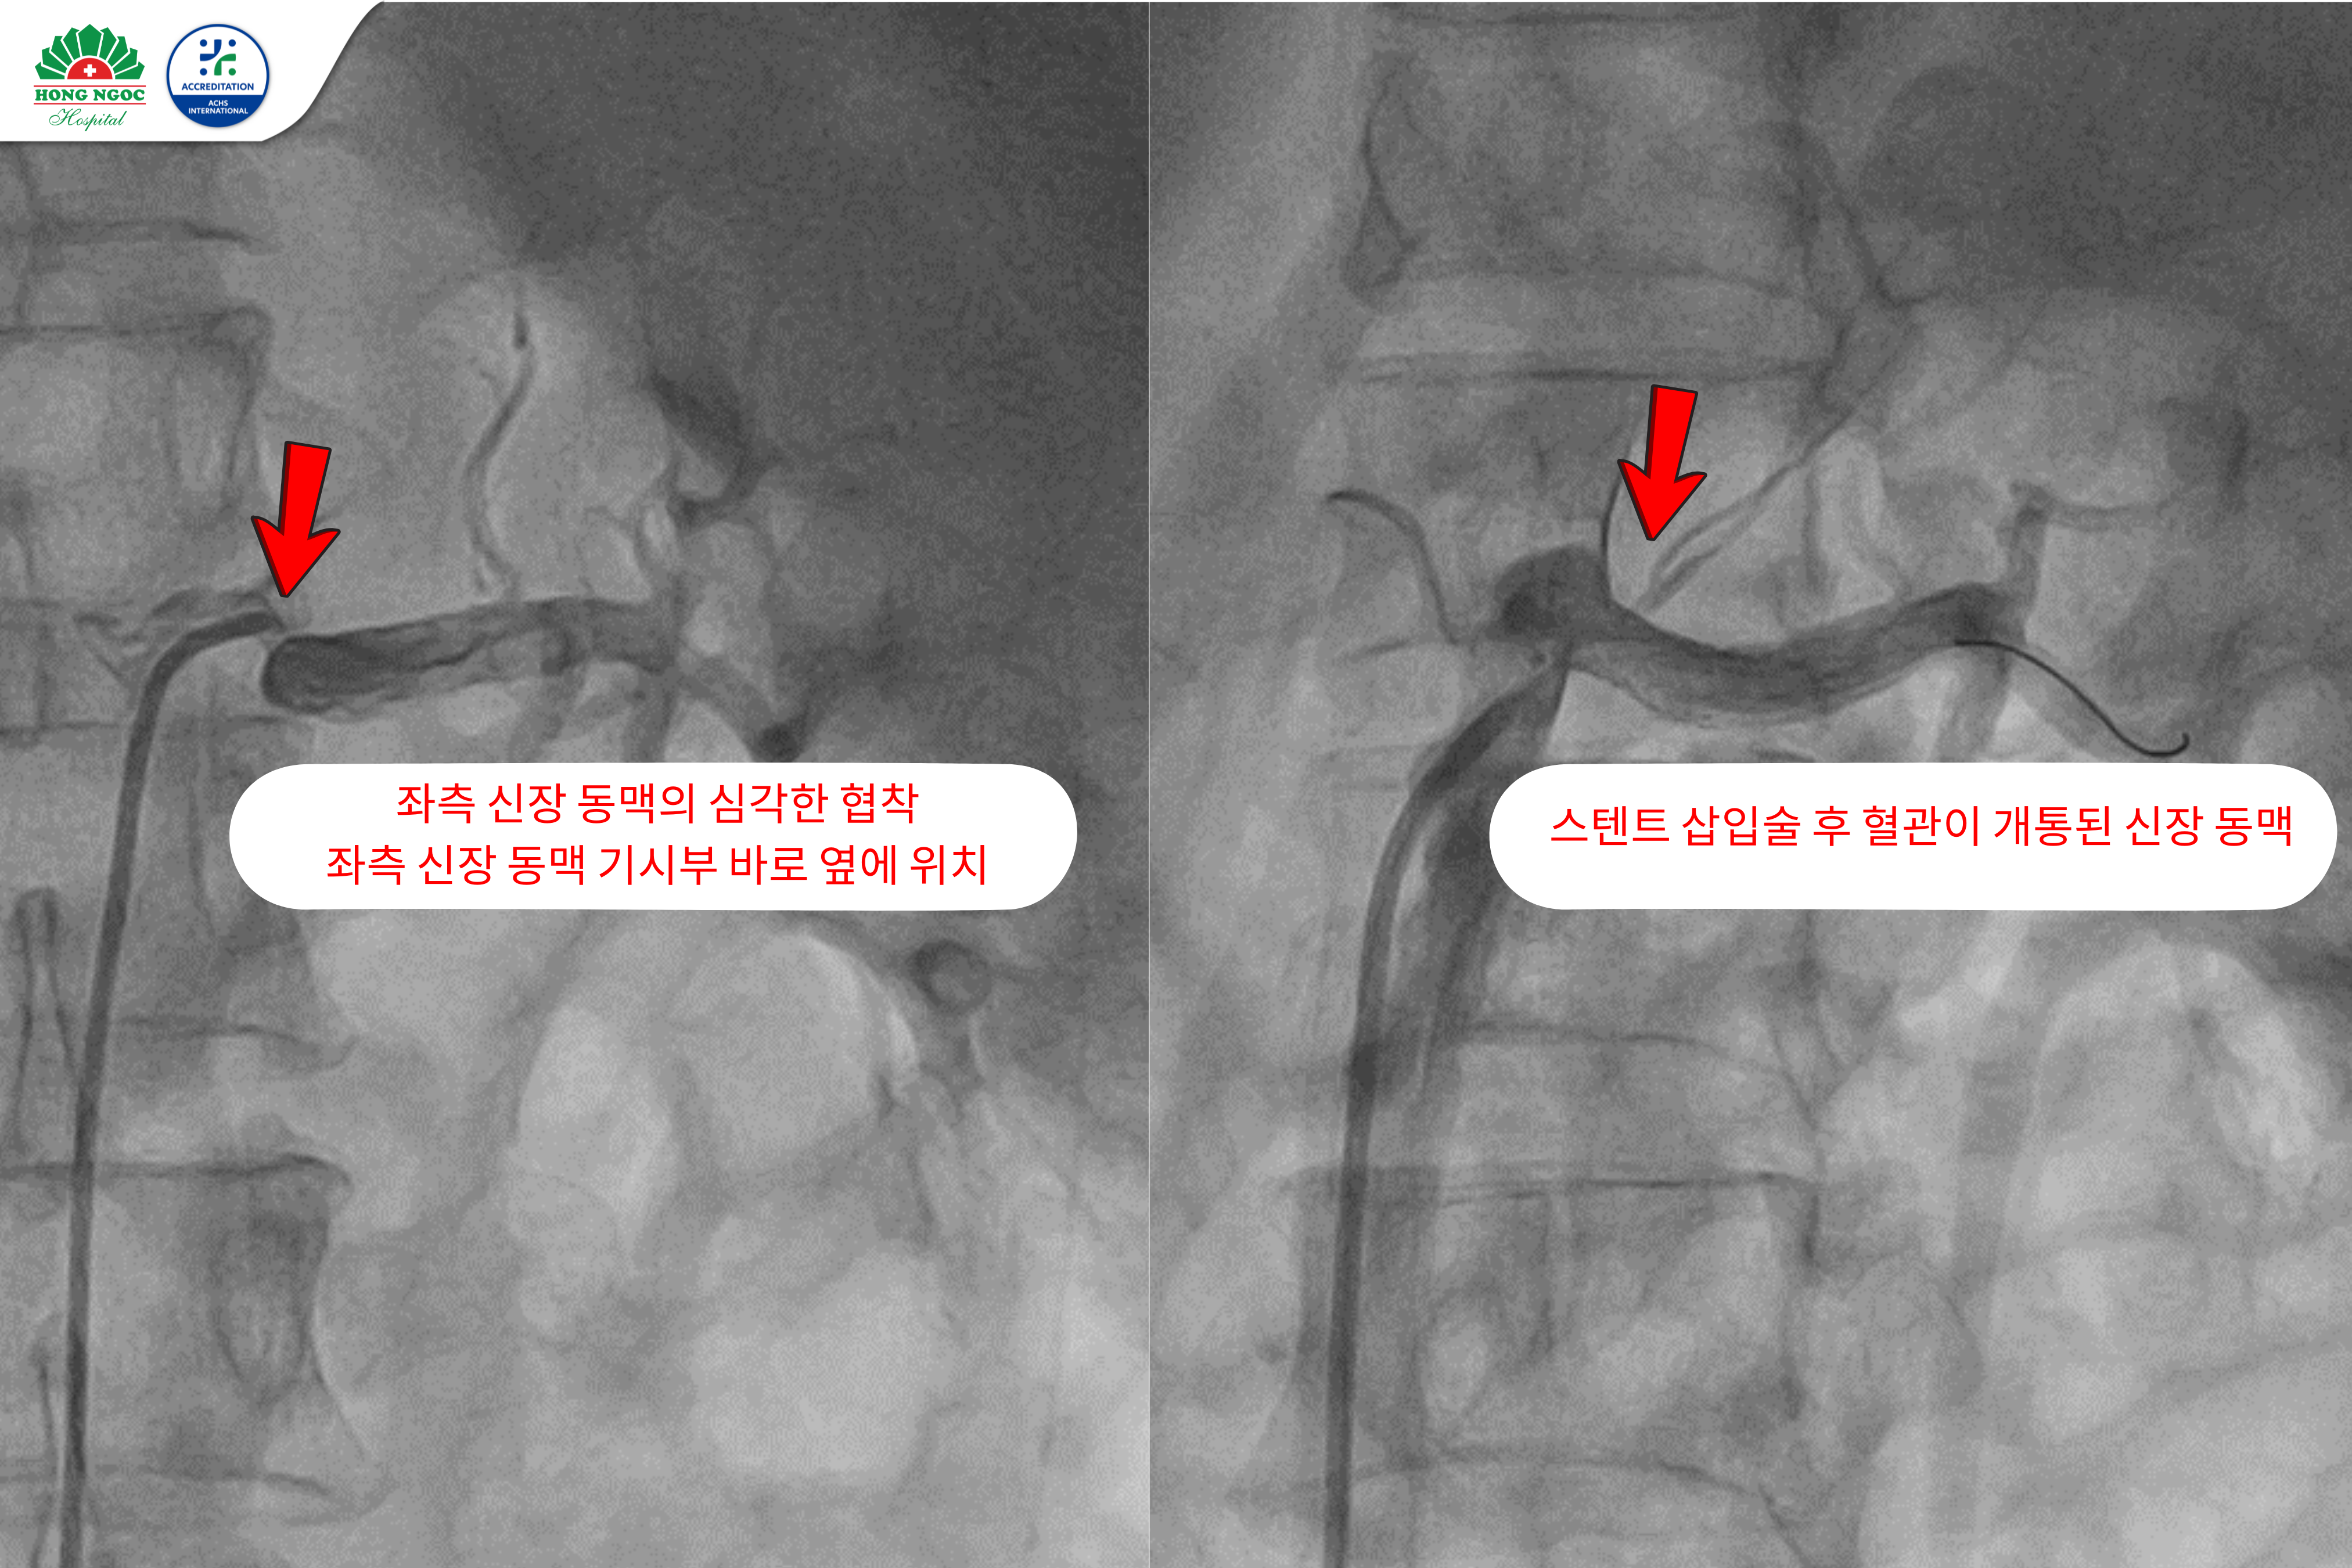

왼쪽 신장동맥 스텐트 삽입술 전후 이미지

의료진의 협의 후, 신장 동맥 스텐트 삽입술을 결정했습니다. 이 시술은 첨단 혈관 조영 시스템의 도움을 받아 진행되었으며, 손상 부위를 정확히 평가하기 위해 혈관 내 초음파(IVUS) 장비도 함께 사용되었습니다. 시술은 순조롭게 진행되었고, 스텐트는 정확한 위치에 성공적으로 삽입되었습니다. 이로 인해 신장 동맥의 혈류가 완전히 회복되었습니다.